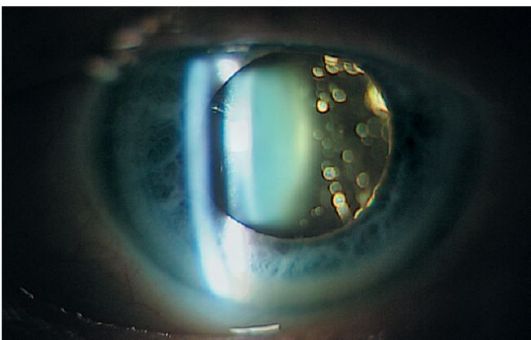

Деструкция стекловидного тела